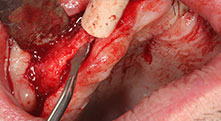

Piezomed B6

Der Kieferkamm wird beidseitig piezochirurgisch gespalten (Instrument: Piezomed B6). Die Implantation erfolgt im selben Eingriff und der periimplantäre Knochen wird zusätzlich mit einer GBR-Maßnahme aufgebaut.